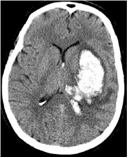

brainCT3 brainCT4

We have developed a unified method to detect both types of strokes from a given CT volume data. The proposed method is based on the observation that stroke presence disturbs the natural contra-lateral symmetry of a slice. Accordingly, we characterize stroke as a distortion between the two halves of the brain in terms of tissue density and texture distribution.